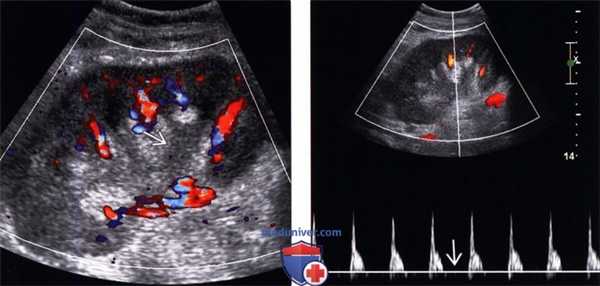

(Левый) На продольном УЗ срезе с цветовой допплерографией трансплантата почки с олигоурией в результате острого отторжения визуализируется диффузное снижение цветового потока. Уротелий почечной лоханки утолщен.

(Правый) На продольном УЗ срезе с импульсно-волновой допплерографией того же трансплантата почки визуализируется артериальная волна с высоким индексом резистентности и отсутствием тока в диастолу.